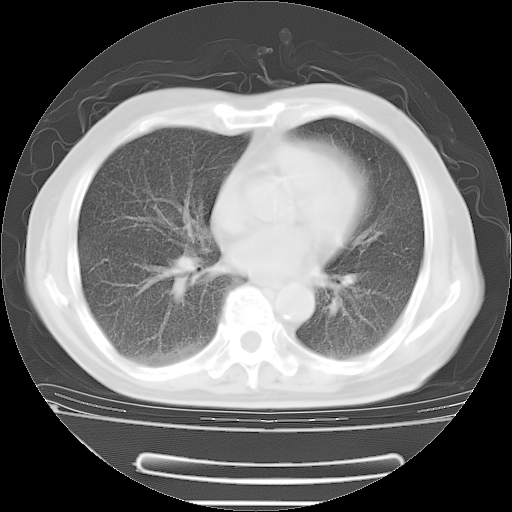

今天复查肺部CT,发现双肺广泛磨玻璃样改变。所以我把3月19日和5月9日相隔50天的肺部CT上传。请大家会诊。

5月9日肺部CT(在4月27日齐鲁医院肺部CT描述部分肺组织磨玻璃样改变,12天后肺组织广泛磨玻璃样改变)

大致读了系列胸部CT:纵隔窗无明显异常,肺窗:从4、27至今:主要是双肺中下野外带可见毛玻璃样改变,目前处于急性肺泡炎阶段,至于原因考虑1、结替组织或胶原血管性疾病所致?2、恶性疾病如恶组在肺部所致的表现或细支气管肺泡癌?3、药物或其它原因如肺蛋白沉着症所致肺泡炎目前不太可能?总之,明天就去请我院的呼吸科、感染科、血液科和临免专家会诊哈。